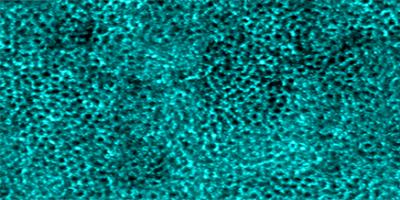

neuron vessels

Inner retinal capillaries (top) and choriocapillaris (bottom) imaged in a living human eye using multimodal adaptive optics enhanced indocyanine green angiography.

Read the associated publication.